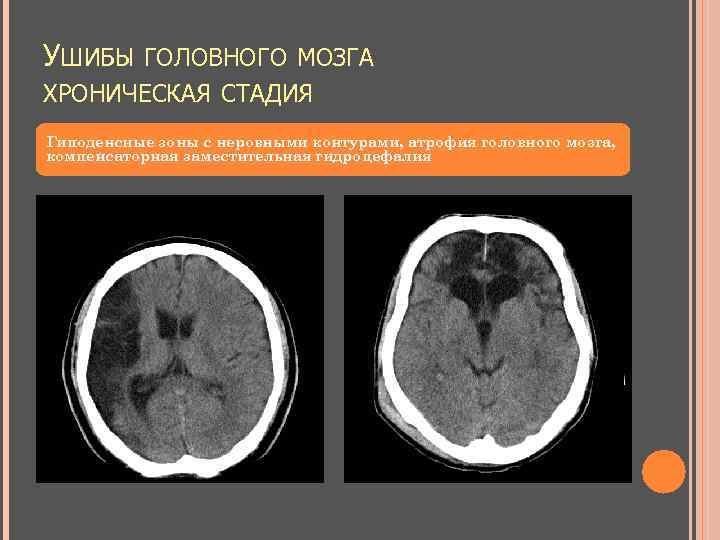

УШИБЫ ГОЛОВНОГО МОЗГА ХРОНИЧЕСКАЯ СТАДИЯ Гиподенсные зоны с неровными контурами, атрофия головного мозга, компенсаторная заместительная гидроцефалия